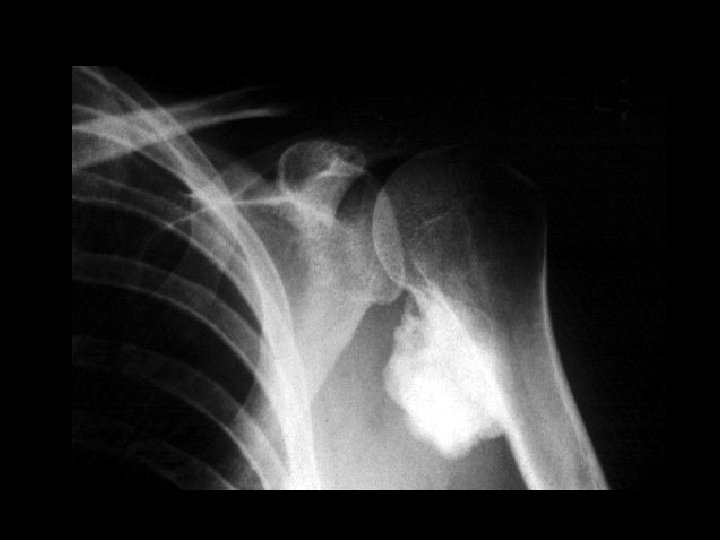

Parosteal osteosarcoma • Findings: – Dense lobular lesion along the medial proximal humerus – No apparent cortical destruction (check w/ CT) • ddx: – NONE! – This is an Aunt Minnie!